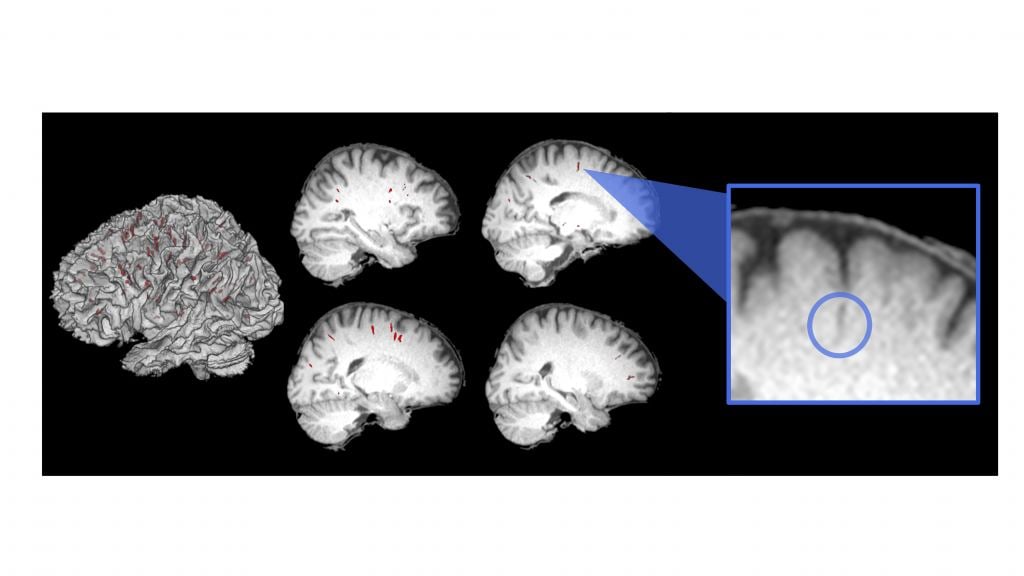

Piantino and a group of researchers just published a study called "Longitudinal MRI-visible perivascular (PVS) changes with long-duration spaceflight". In it, they discuss obvious brain changes in astronauts. "These findings have important implications as we continue space exploration," said Piantino, in a press release statement. "It also forces you to think about some basic fundamental questions of science and how life evolved here on Earth."

Researchers decided to find out by measuring the perivascular spaces in astronaut brains. These are where cerebrospinal fluid flows in the brain. They are part of a system-wide brain cleansing that occurs during sleep called the "glymphatic system". Among other things, it clears metabolic proteins that would otherwise build up in the brain. Scientists say this system seems to perform optimally during deep sleep. So, the question was: how would it change in space?

Piantino and his collaborators examined magnetic resonance imaging scans of 15 astronauts both before and after their extended stays on the International Space Station. Each space traveler had several scans: one before launch and one after they got back home on Earth. Then, they had additional scans one, three, and six months after their missions. All those MRIs got compared to the brains of people who had never been to space.

The differences were pretty interesting, and a bit unexpected in one way. The brains of first-time space travelers showed increases in the perivascular spaces. The brains of old-timers (who had been to space before) didn't show that kind of change. It's fairly clear to Piantino and the team that the experienced space fliers had somehow adapted. They aren't quite sure why. So, that will take further study.